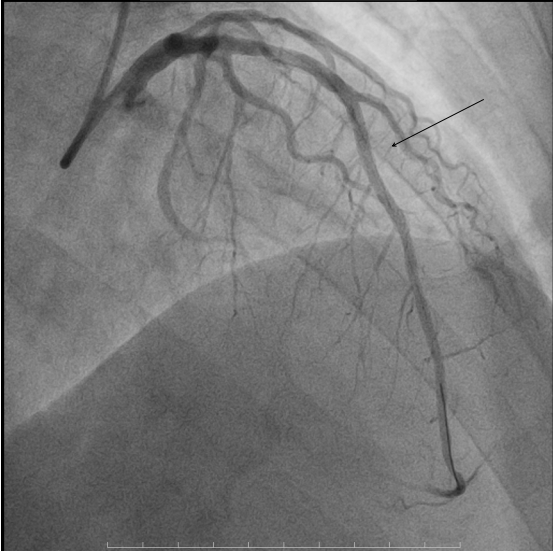

▲术后冠脉造影

术前心电图同样反映出该病症的相关特征。入院后急诊冠脉造影发现,前降支近段存在50%局限性狭窄,中段节段性病变,且最重狭窄达到90%并可见明显的血栓影。为更精准把握血管内部情况,我院团队进一步行血管内超声检查,结果显示前降支中段可见纤维脂质斑块,最小管腔面积仅为2.11mm²,斑块负荷高达81.5%。面对如此复杂的病情,我院介入团队沉着冷静、有条不紊地开展救治工作,先进行球囊扩张,而后成功植入一枚3.0*30mm支架。术后再次通过血管内超声检查确认,支架贴壁、膨胀良好,最小管腔面积已提升至6.15mm²,手术结果十分满意,患者胸痛症状明显缓解。